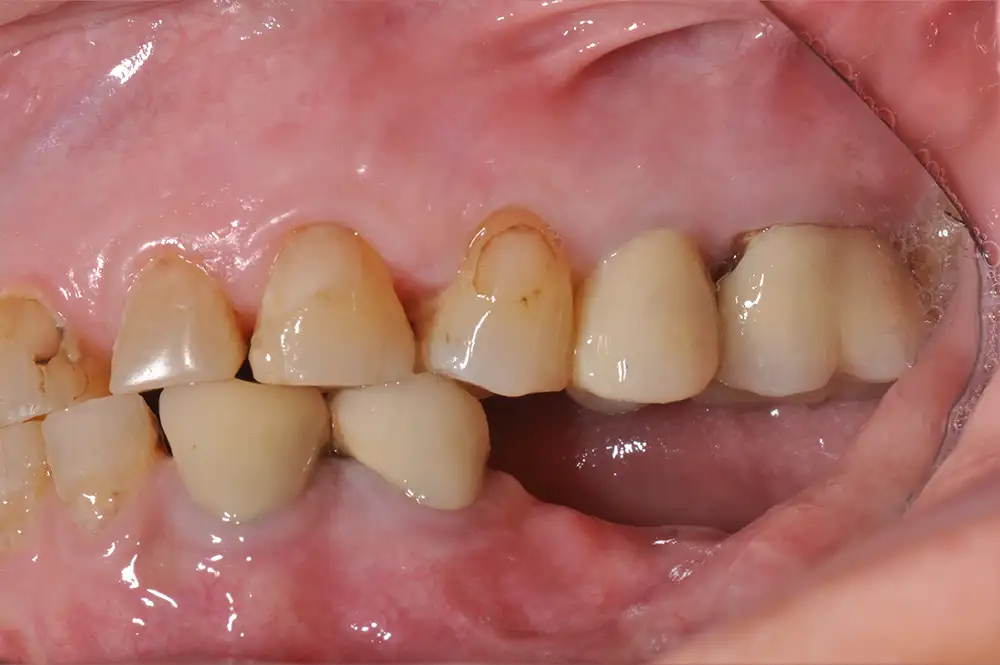

Visione laterale sinistra iniziale

Nella relative foto del sorriso iniziale i denti appaiano piccoli e lasciano trasparire un enorme buco nero antiestetico. La situazione veniva peggiorata anche dalla presenza di diastemi (denti distanziati). Sul lato inferiore sinistro esisteva il problema opposto, ponte ormai ventennale, ma inestetico e con dinamica masticatoria inadatta in quanto troppo voluminoso rispetto alla grandezza naturale dei suoi denti.

L’usura dei denti aveva comportato anche un inestetismo a livello labiale, determinandone l’accartocciamento a bocca chiusa.

La condizione clinica era ulteriormente peggiorata dalla estrema fragilità di tutti i denti in quanto oggetto di microfratture.